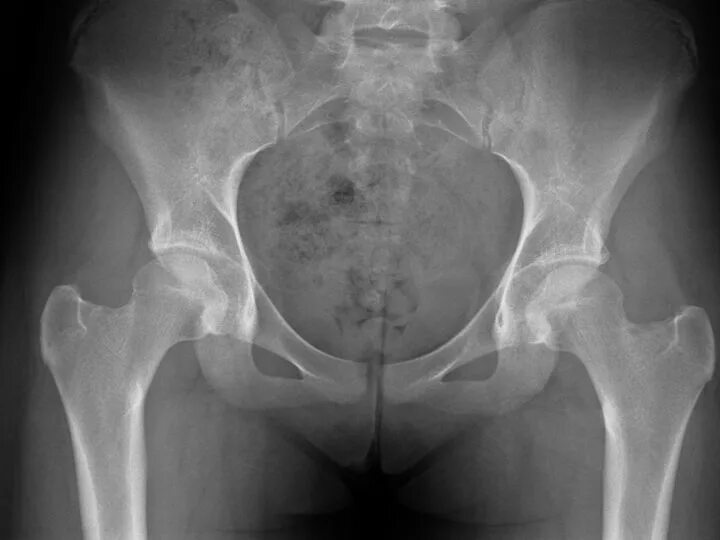

Остеоартроз тазобедренных суставов 1 2